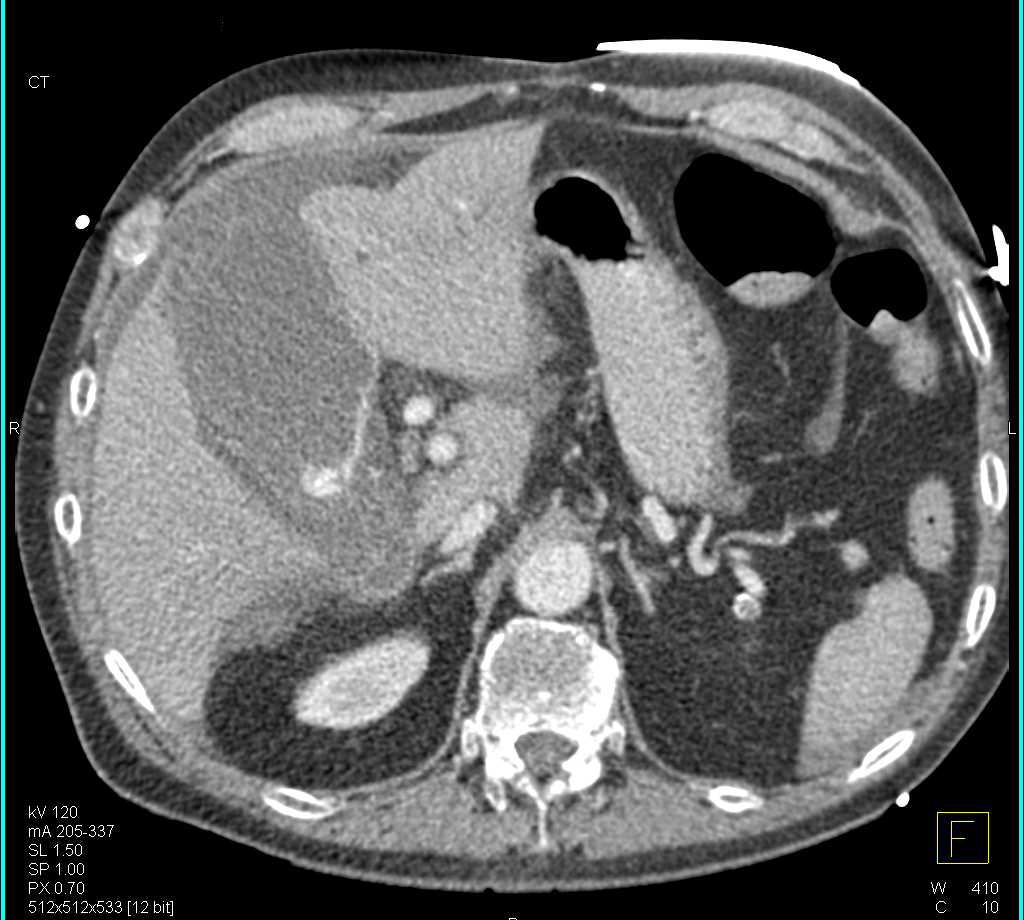

Ampullary Stricture due to Carcinoma at Ampulla